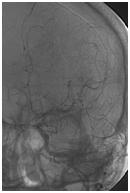

Mujer de 46 años que ingreso por cefalea súbita, hemiparesia izquierda y disartria, con tomografía axial computarizada cerebral simple que mostró hemorragia frontoparietal derecha drenada a ventrículos y arteriografía con patrón Moyamoya. Reingreso 3 meses después con deterioro del estado de consciencia y tomografía axial computarizada cerebral simple que mostró hemorragia intraparenquimatosa temporoparietal izquierda con extensión intraventricular y desviación de la línea media, se manejo en Unidad de Cuidados Intensivos con traqueostomía y gastrostomía, presentó neumonía y sepsis nosocomial, finalmente falleció en la Unidad de Cuidados Intensivos.